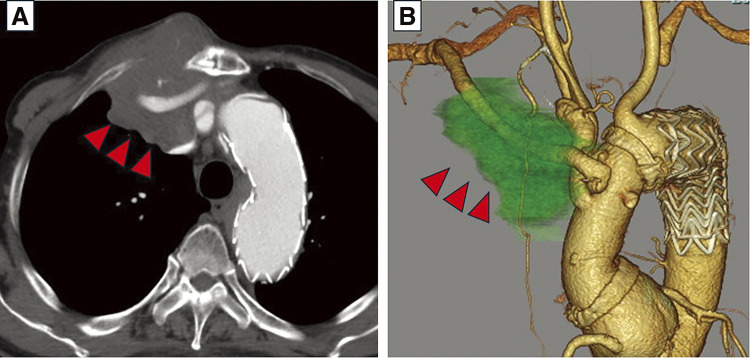

患者男,76岁,2年前行胸腔血管内主动脉修复术后逆行A型主动脉夹层右腋窝动脉搭桥及弓置换术,主诉右侧锁骨下区肿胀疼痛。计算机断层扫描怀疑旁路移植周围有脓肿;然而,文化是消极的。病理检查显示弥漫性大b细胞淋巴瘤(DLBCL)。由于患者病情不适合化疗,3个月后去世。起源于移植物周围的DLBCL极为罕见,但对鉴别诊断至关重要。

A 76-year-old male patient, who had undergone right axillary artery bypass and arch replacement surgery for retrograde type A aortic dissection after thoracic endovascular aortic repair 2 years ago, was referred to our department with complaints of swelling and pain in the right subclavian region. A computed tomography scan suspected an abscess around the bypass graft; however, the culture was negative. Pathological examination indicated a diffuse large B-cell lymphoma (DLBCL) diagnosis. Chemotherapy was not indicated due to the patient's condition, and he passed away after 3 months. DLBCL originating around a graft is extremely rare but crucial for differential diagnosis.